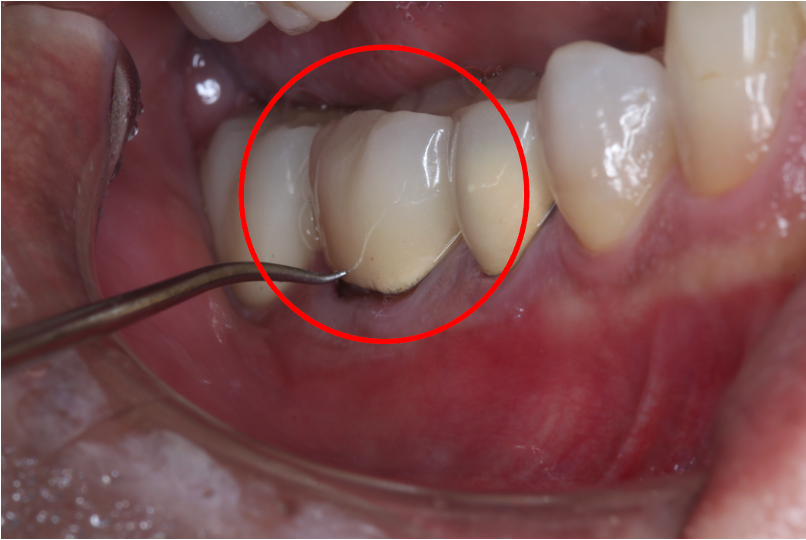

セラミック症例③

年齢30代女性

治療期間1ヶ月

治療内容セラミックインレー

治療箇所右下4番

治療費用100,000円